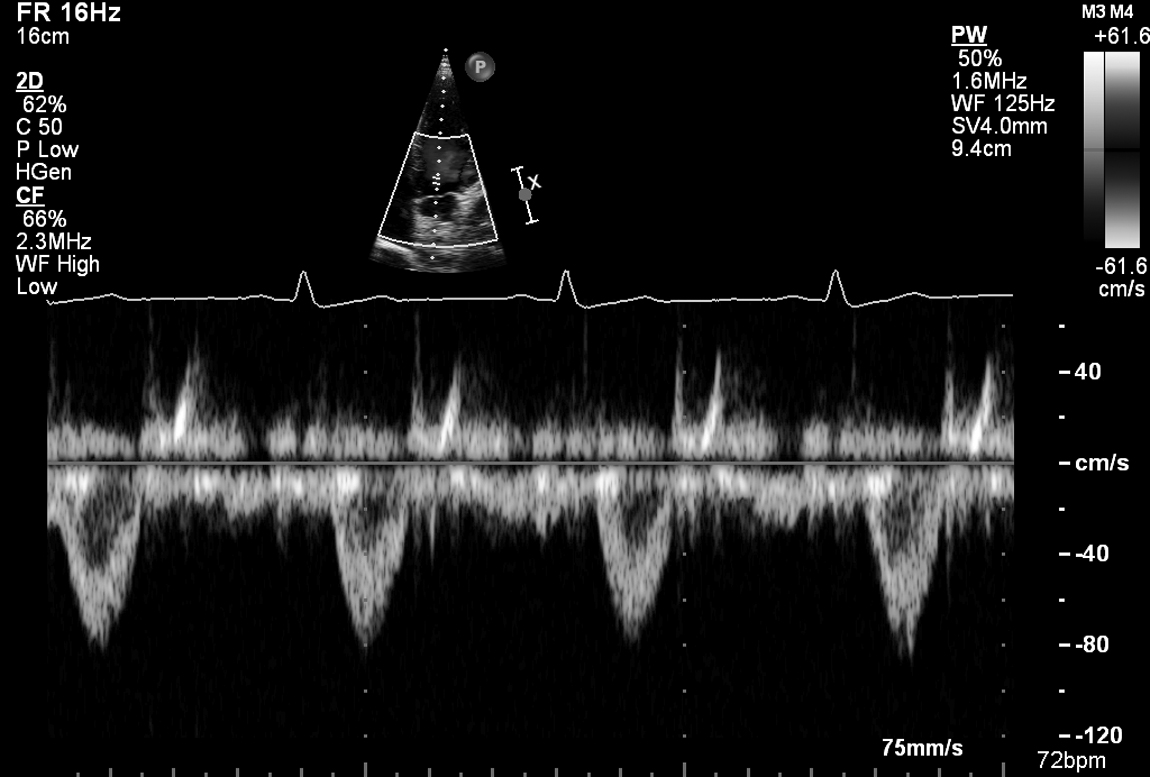

A 35-year-old woman presents with worsening exertional dyspnoea over 3 months following a viral illness. She has no chest pain. She is a non-smoker. ECG shows LBBB. The basal septum thickness is 0.5 cm and the LV is 6 cm at end-diastole. Peak LVOT velocity is 0.8 m/s and peak aortic velocity is 1.2 m/s. Her echo is shown in Fig 5.1, 5.2 and Videos 5.1, 5.2, 5.3, 5.4, 5.5, 5.6, 5.7, 5.8, 5.9, 5.10 and 5.11.